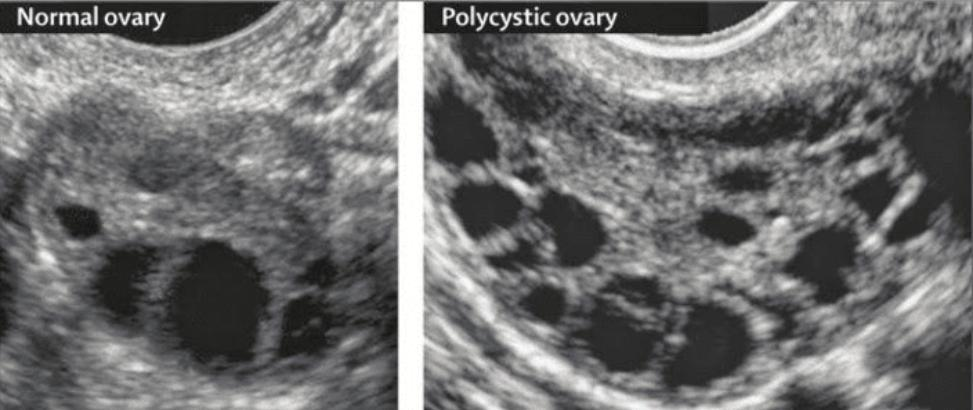

Polycystic Ovary Syndrome (PCOS) is a chronic hormonal condition that affects millions of women worldwide, especially those in their reproductive years.

💖 Get checked – If you suspect you have PCOS, don’t delay. Consult your OB-GYN and ask for hormonal tests or an ultrasound.